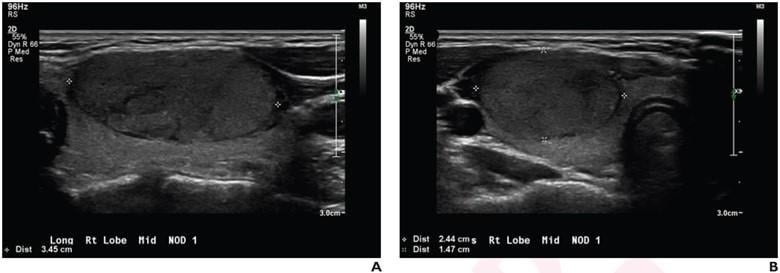

Longitudinal and transverse grayscale ultrasound images of thyroid nodule in 17-year-old patient with benign follicular adenoma, based on surgical excision alone. Overall impression for all three radiologists was benign (true negative). ACR TI-RADS recommendation for all three radiologists was FNA (false positive). Deep learning algorithm recommendation was FNA (false positive).

October 21, 2022 — According to an accepted manuscript published in ARRS’ American Journal of Roentgenology (AJR), ACR TI-RADS and a deep learning algorithm trained on adult populations offer alternative strategies for evaluating thyroid nodules in children and younger adults, including guiding decisions to perform fine-needle aspiration.

“Both ACR TI-RADS and the deep learning algorithm had higher sensitivity, albeit lower specificity, compared with radiologists’ overall impressions,” wrote co-first author Jichen Yang, BSE, from the department of electrical and computer engineering at Duke University in Durham, NC.  Adding that the algorithm had similar sensitivity, but lower specificity, than ACR TI-RADS, “interobserver agreement was higher for ACR TI-RADS than for overall impressions,” Yang noted.

In this AJR accepted manuscript, 139 patients (119 female, 20 male) aged ≤21 years with a thyroid nodule on ultrasoundwith definitive pathologic results from fine-needle aspiration and/or surgical excision were evaluated from January 1, 2004 to September 18, 2020. Single transverse and longitudinal images of one nodule per patient were then extracted. Three radiologists independently characterized nodules based on overall impression (benign vs. malignant) and ACR TI-RADS. A previously developed deep learning algorithm determined malignancy likelihood for each nodule, which was used to derive risk level.

Ultimately, for evaluating thyroid nodules via ultrasound in children and young adults, radiologists’ overall impressions—representing the current standard clinical approach—had mean sensitivity of 58.3% and mean specificity of 79.9%; ACRTI-RADS had mean sensitivity of 85.1% and mean specificity of 50.6%, and a deep learning algorithm had sensitivity of 87.5% and specificity of 36.1%.

“Given the heightened priority for sensitivity when evaluating thyroid nodules in children, compared with in adults, the findings support the continued exploration in children of ACR TI-RADS and of the deep learning algorithm,” Yang et al. concluded in this AJR accepted manuscript